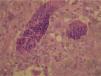

HistopatologíaEl examen macroscópico mostró una tumoración nodular de color pardo-amarillento. El estudio histopatológico demostró una neoplasia multinodular, parcialmente rodeada por una cápsula fibrosa. Estaba constituida por histiocitos ovalados y de núcleo vesiculoso, mezclados con células gigantes multinucleadas prominentes dentro de un estroma hialinizado y fibroso. Además, existían células espumosas, siderófagos y células mononucleares (figs. 2 y 3).

El estudio anatomopatológico muestra una neoplasia habitualmente multinodular formada por células histiocitarias ovaladas y de núcleo vesiculoso, que se mezclan con células gigantes multinucleadas prominentes, células espumosas, siderófagos y células mononucleares aisladas. Otros hallazgos frecuentes son la hialinización intensa del estroma, los depósitos de hemosiderina y la presencia de cristales de colesterol4. Hay que hacer el diagnóstico diferencial con el fibroma de la vaina tendinosa, que posee un estroma muy hialinizado y escasas o ausentes células gigantes multinucleadas4,5.